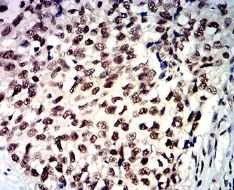

HDAC1 Mouse Monoclonal antibody[1B6A7]

IHC    1/200 - 1/1000